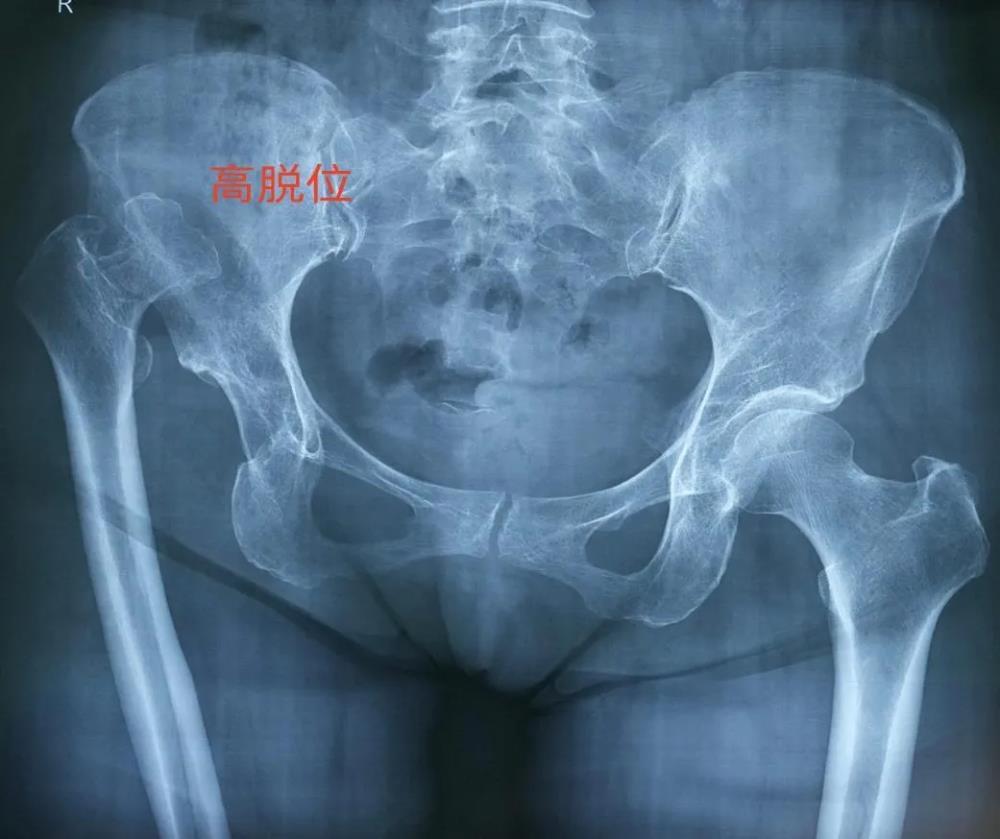

发育性髋关节发育不良(DDH)的 Crowe IV 型是该疾病中最为严重的亚型,主要表现为股骨头完全脱出真性髋臼,伴有显著的髋关节结构异常及下肢严重短缩。由于此类型存在极大的解剖结构变异,对其进行人工全髋关节置换术的技术难度极高、操作复杂,被视为该领域最具挑战性的手术之一,因而常被称作人工全髋关节置换界的“珠穆朗玛峰”。

近日,陆川县63岁的邹女士因为右髋关节疼痛、跛行伴随右下肢明显短缩已长达六十年,长期行动不便与日益加重的疼痛严重影响了她的生活质量,简单的行走都成为一种奢望。经多方打听,邹女士慕名来到我院髋关节一科就诊,寻求最后的希望。经我院髋关节一科团队详细检查,邹女士诊断为右侧发育性髋关节发育不良(DDH)Crowe IV型,完善术前检查,并计划行人工全髋关节置换术。